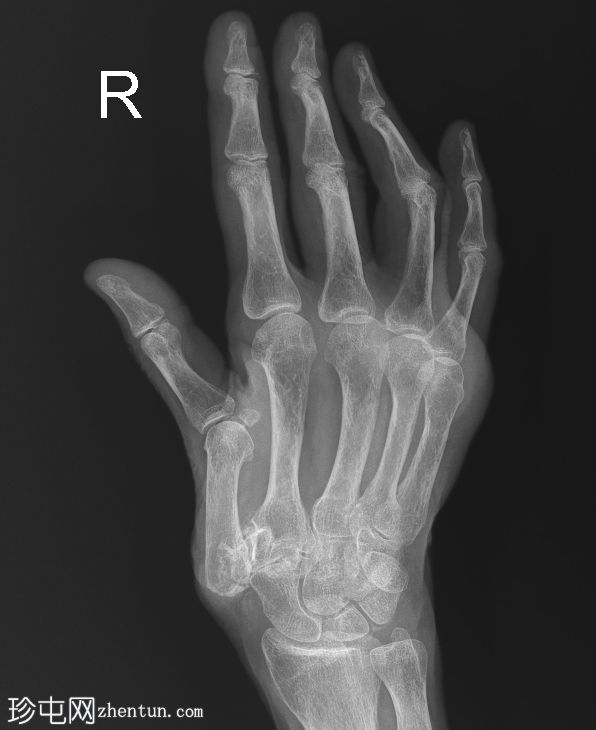

右手X线片

X线片

正位

小指近节指骨干轻微移位螺旋形骨折,周围软组织肿胀。怀疑拇指掌骨基底部和大多角骨骨折。

第一腕掌关节脱位,周围软组织肿胀。

第二至第五腕掌关节正常。桡腕关节、掌指关节和指间关节正常。尺骨茎突正常。

骨密度降低。